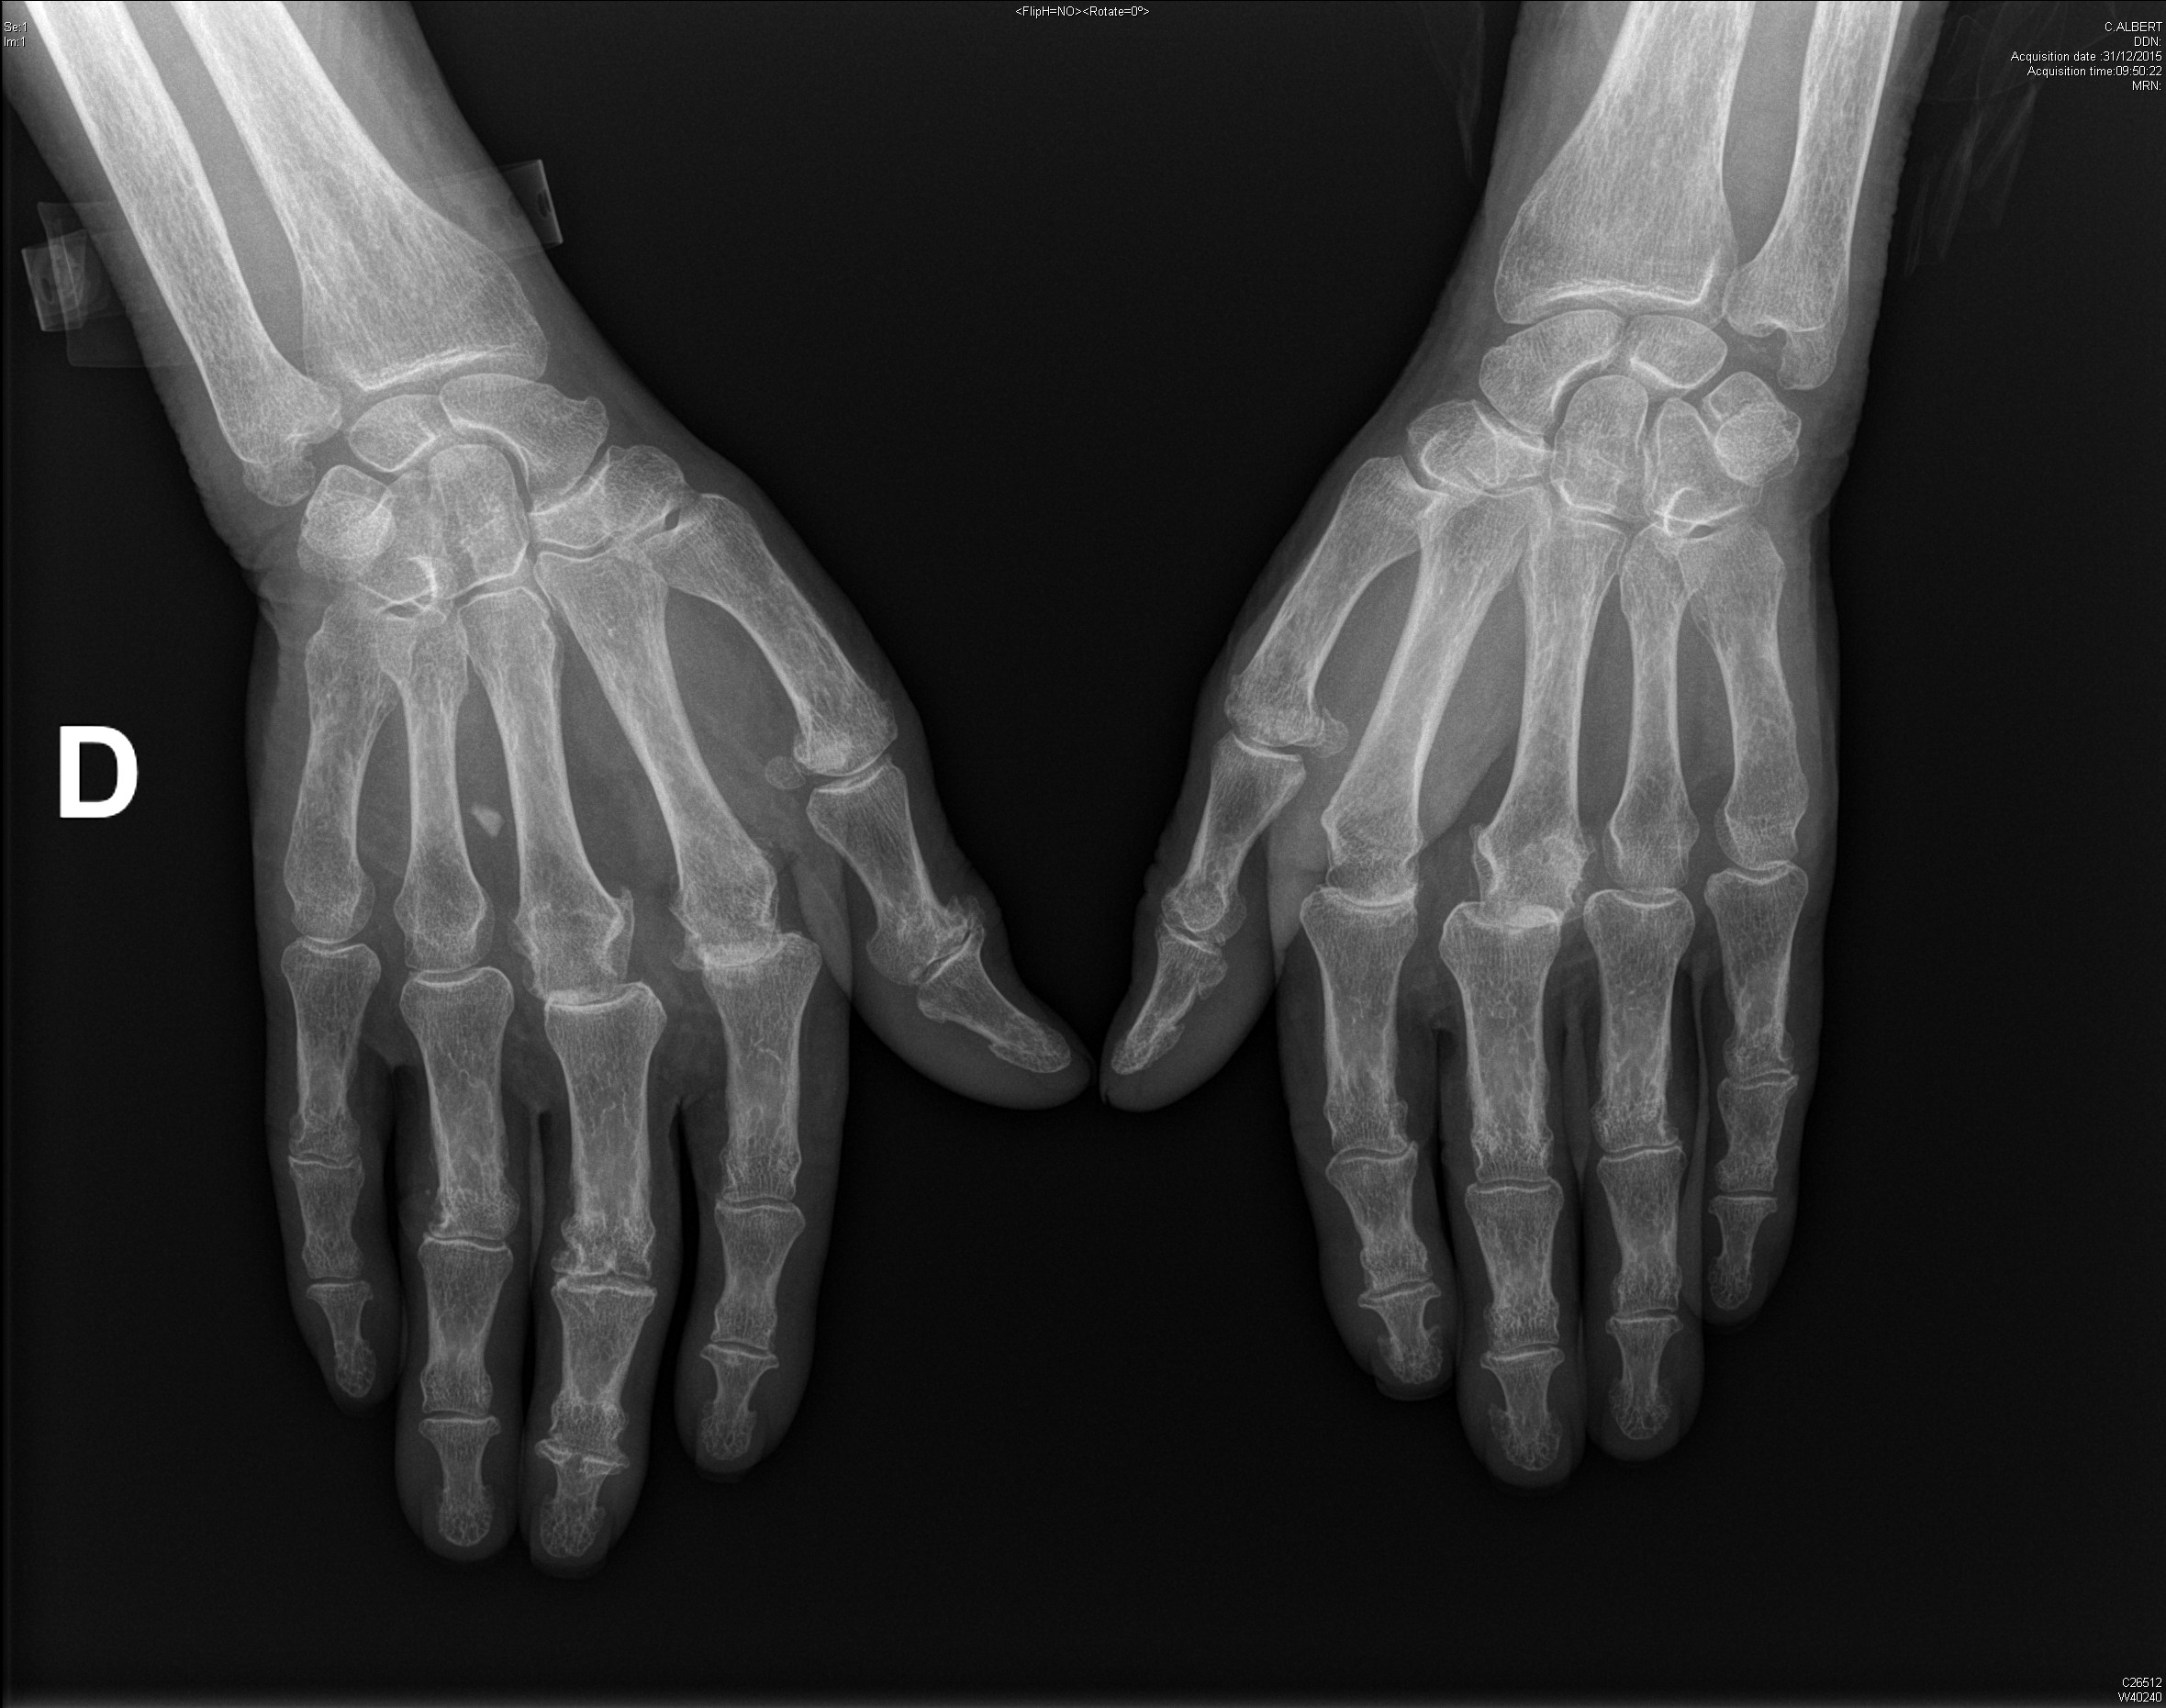

Carpite bilatérale évoluée dans le cadre d'une polyarthrite rhumatoïde